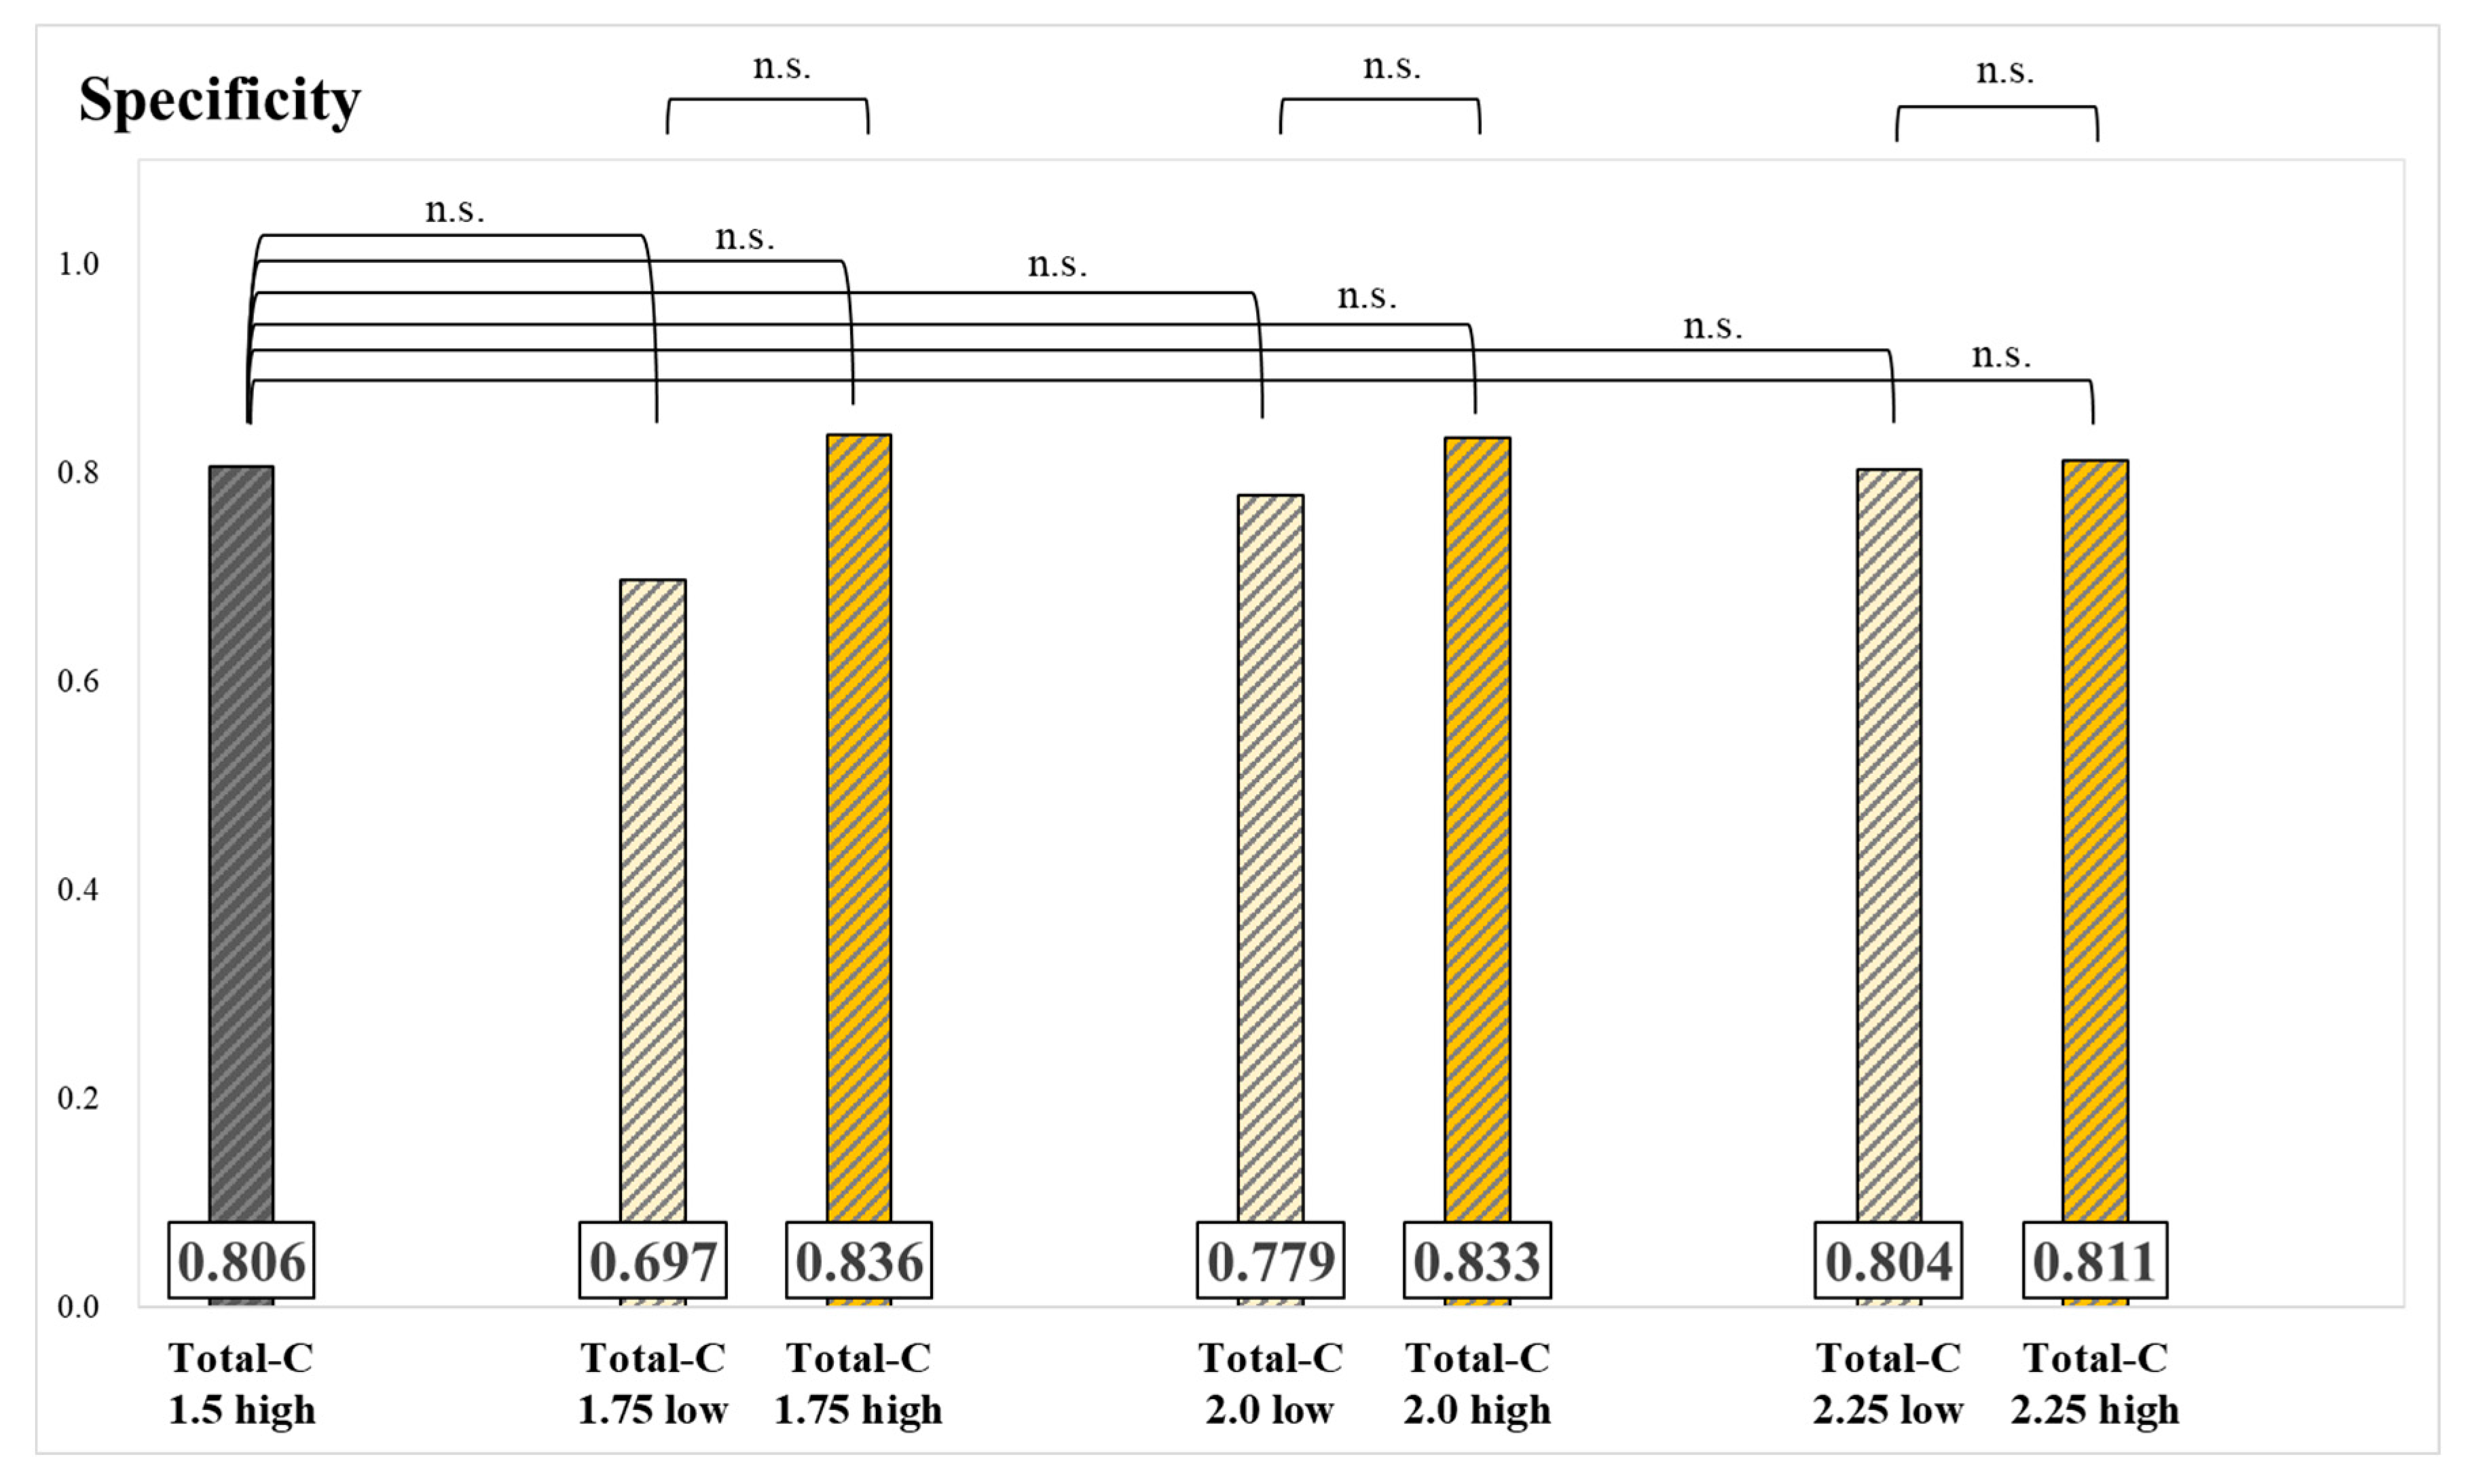

3. Results

4. Discussion